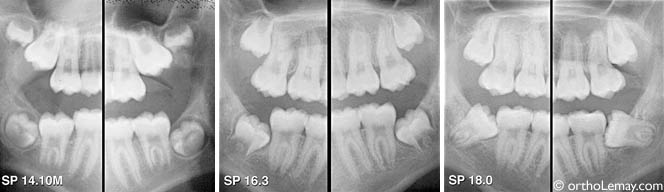

évolution sur 6 ans

Évolution de la position des dents de sagesse inférieures pendant une période de 6 ans. Dès qu’il est évident que les dents ne sortiront pas convenablement, il serait préférable de les extraire pour éviter que l’intervention (extraction) soit plus complexe plus tard (pour le patient et le chirurgien).

(A) À 15 ans, les dents de sagesse inférieures sont déjà inclinées vers l’avant.

(B) 3 ans plus tard, les dents basculent davantage vers l’avant. Il n’y a pas assez de croissance à l’arrière de la mandibule pour permettre un redressement des molaires incluses et permettre leur éruption. Il serait indiqué de faire extraire ces molaires à ce moment, car il est impossible que ces dents sortent convenablement. Les dents de sagesse supérieures continuent de pousser, mais celle de gauche demeure bloquée derrière la deuxième molaire.

(C) À 21 ans, les dents de sagesse inférieures sont rendues horizontales, ce qui compliquera leur extraction.